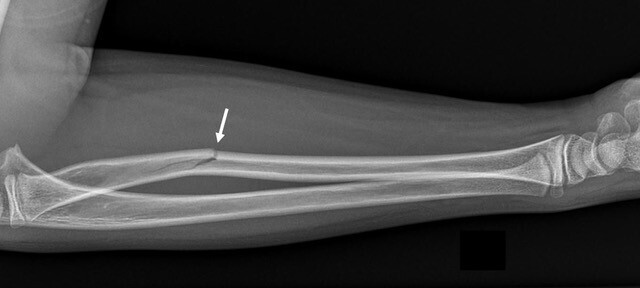

• fracture en bois vert : une corticale est pliée mais continue alors que l’autre est rompue (fig. 4) ;

• fracture « plastique » ou « arcuature » : il n’y a pas de fracture mais une courbure plastique s’étendant sur toute la longueur de l’os (fig. 5) ;